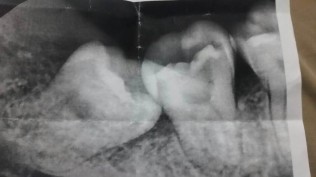

左边这颗是右下八号牙,智齿长歪了,导致七号牙顶坏了痛不行,相接处好像有虫洞了,果断决定切割智齿拔掉!

切开,拔掉!智齿,想死!还有三颗!